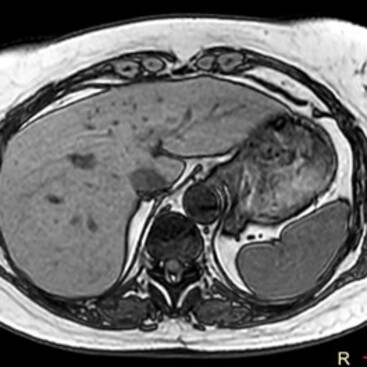

Die MRT (Magnetresonanztomographie), auch Kernspintomographie genannt, ist eine Untersuchung in einem Magnetfeld und benötigt keine Röntgenstrahlen. Mit ihr können alle Körperregionen überlagerungsfrei dargestellt werden. Wir führen hier die MRT fast aller Körperregionen, Organe und Blutgefäße durch.